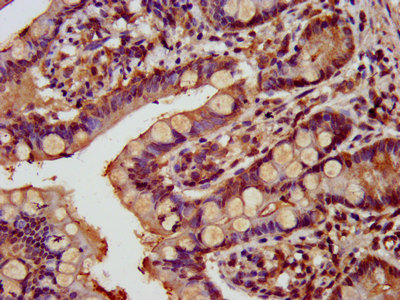

IHC image of CSB-PA803156LA01HU diluted at 1:800 and staining in paraffin-embedded human small intestine tissue performed on a Leica BondTM system. After dewaxing and hydration, antigen retrieval was mediated by high pressure in a citrate buffer (pH 6.0). Section was blocked with 10% normal goat serum 30min at RT. Then primary antibody (1% BSA) was incubated at 4°C overnight. The primary is detected by a biotinylated secondary antibody and visualized using an HRP conjugated SP system.